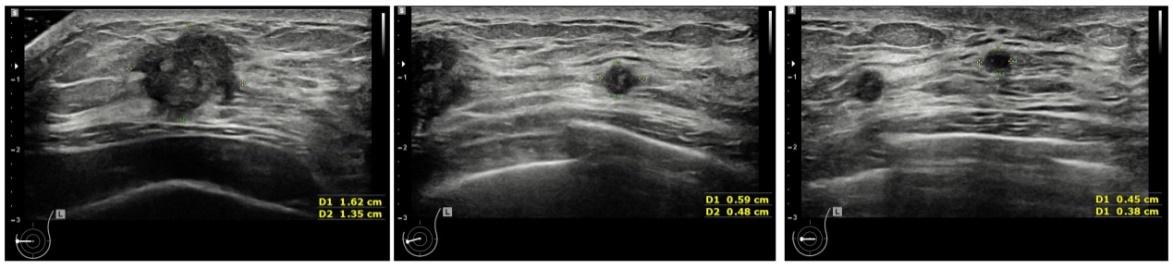

超声科大夫复查了超声(图1),结果发现左乳除了之前提示的内象限9点结节外,旁边还有两个可疑恶性的结节。幸运的是,淋巴结没有看到可疑的转移征象。

图1 乳腺超声提示左侧乳腺多发可疑恶性肿物

左侧图像为之前穿刺的恶性结节,中间和右侧图像为穿刺结节旁肿物 。